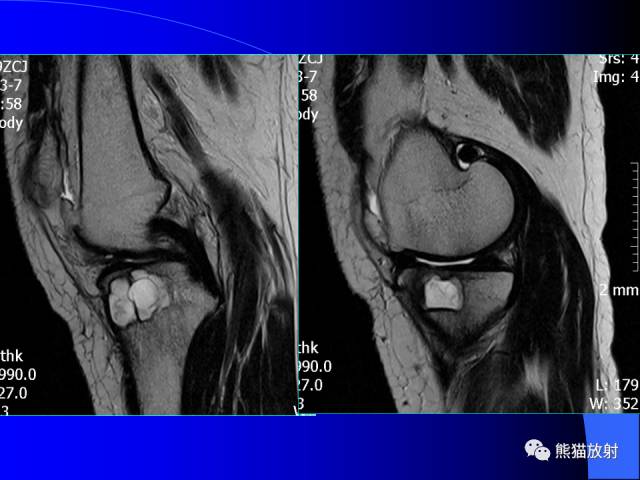

膝关节周围囊肿是较常见的病变,可以是原发的,多见于青年及儿童,囊内容物通常是黏液;也可以是继发的,多与关节腔相通,内含一般黏性的滑液,常继发于膝关节骨关节炎、类风湿关节炎、非特异性滑膜炎、半月板损伤、髌骨软骨软化症等。